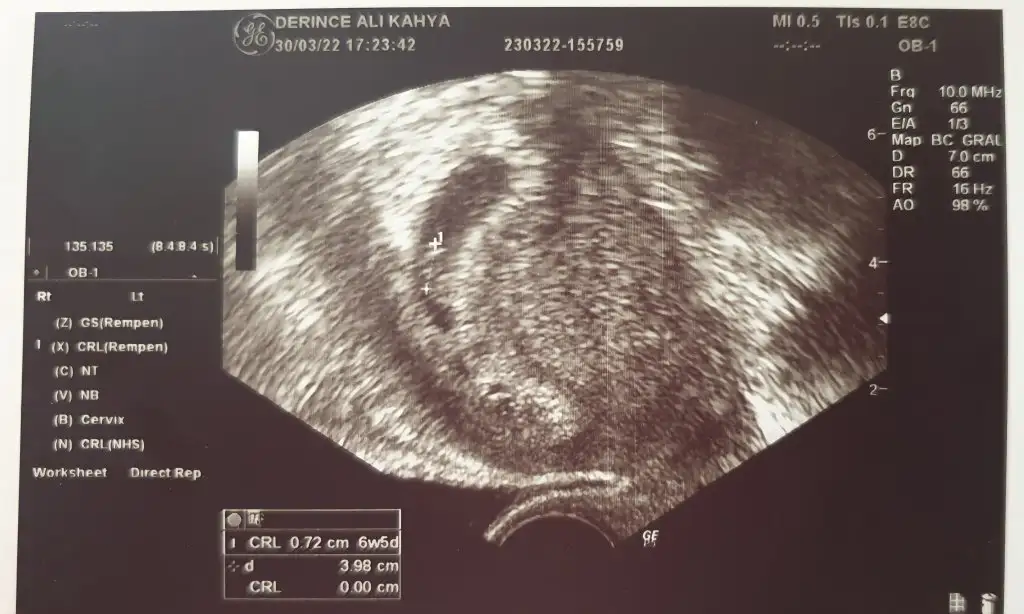

kuzum embriyo göremedim ben5+4 karından

Yok zatenkuzum embriyo göremedim ben